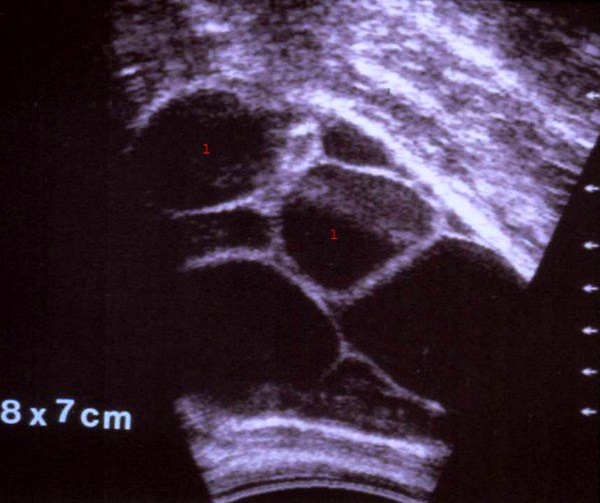

Ultralyd af æggestok med cyster

aeggestok-theca lutein cyster-ultralyd

1. Fler-kamret cyste i æggestokken påvist ved ultralydskanning